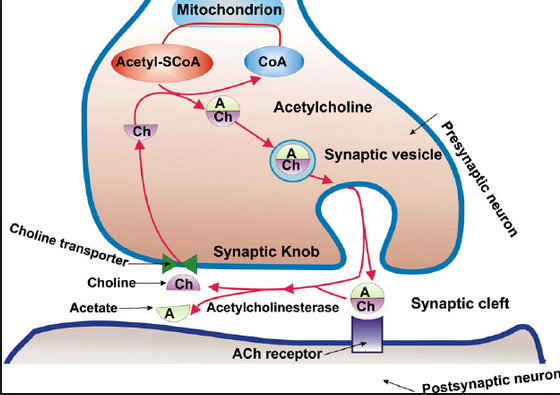

and the LINK to the bio-molecular communications molecule ……ace –> acetylcholine

Acetylcholine – Wikipedia, the free encyclopedia

https://en.wikipedia.org/wiki/Acetylcholine

Wikipedia

Acetylcholine is an organic chemical that functions in the brain and body of many types of animals, including humans, as a neurotransmitter—a chemical …

History · Function · Synthesis and degradation · Receptors

Acetylcholine Neurotransmission (Section 1, Chapter 11 …

neuroscience.uth.tmc.edu › Table of Contents

11.1 Introduction. Acetylcholine, the first neurotransmitter discovered, was originally described as “vagus stuff” by Otto Loewi because of its ability to mimic the …

Acetylcholine – Neuroscience – NCBI Bookshelf

www.ncbi.nlm.nih.gov › … › Bookshelf

National Center for Biotechnology Information

by D Purves – 2001

Acetylcholine is the neurotransmitter at neuromuscular junctions, at synapses in the ganglia of the visceral motor system, and at a variety of sites within the …

Choline transporter —> newspaper messages via –> Cho + line –> Mr. Cho an English major and Virginia tech and his line(s) …. choline messages

Acetylcholine – Wikipedia, the free encyclopedia

https://en.wikipedia.org/wiki/Acetylcholine

Wikipedia

Acetylcholine is an organic chemical that functions in the brain and body of many types of ….. The enzyme acetylcholinesterase converts acetylcholine into the inactive metabolites choline andacetate. This enzyme is abundant in the synaptic …

acetylcholinesterase converts acetylcholine into the inactive metabolites choline and acetate.

the inactive metabolites choline and acetate.

the inactive metabolites choline and acetate.

the inactive metabolites ……………….acetate.

the inactive metabolites ……………….ace …. tate.

Thus ….above we show the ace –> acetylcholine information expression string …. in the EXTERNAL world ..using the EARTH geography surface as an information display screen … like a movie projector.

Thus ….above we show the ace –> acetylcholine information expression string …. in the EXTERNAL world ..using the EARTH geography surface as an information display screen … like a movie projector ….giving…

.the ace –> acetylcholine information expression string …. in the EXTERNAL world ..using the EARTH geography surface as an information display screen …